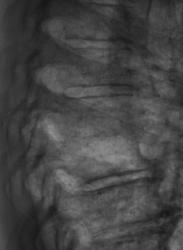

Вчера был почти аналогичный случай.

По второму представленному случаю. У меня складывается впечатление об ограниченной релаксации правой половины диафрагмы, а не о плеврите.

И первого и второго пациентов отдали фтизиатрам. Первого пунктировали. Вторым занимаются. Как будут сведения о "втором" тогда сообщу.